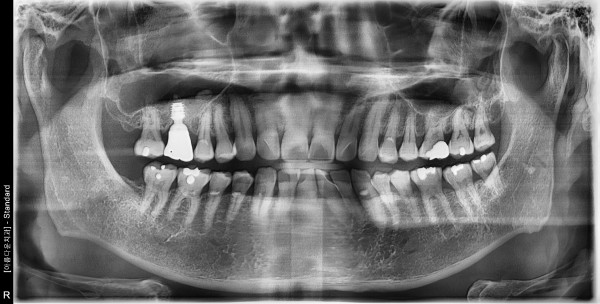

54세 남자 상악 뼈 이식후 임플란트 식립